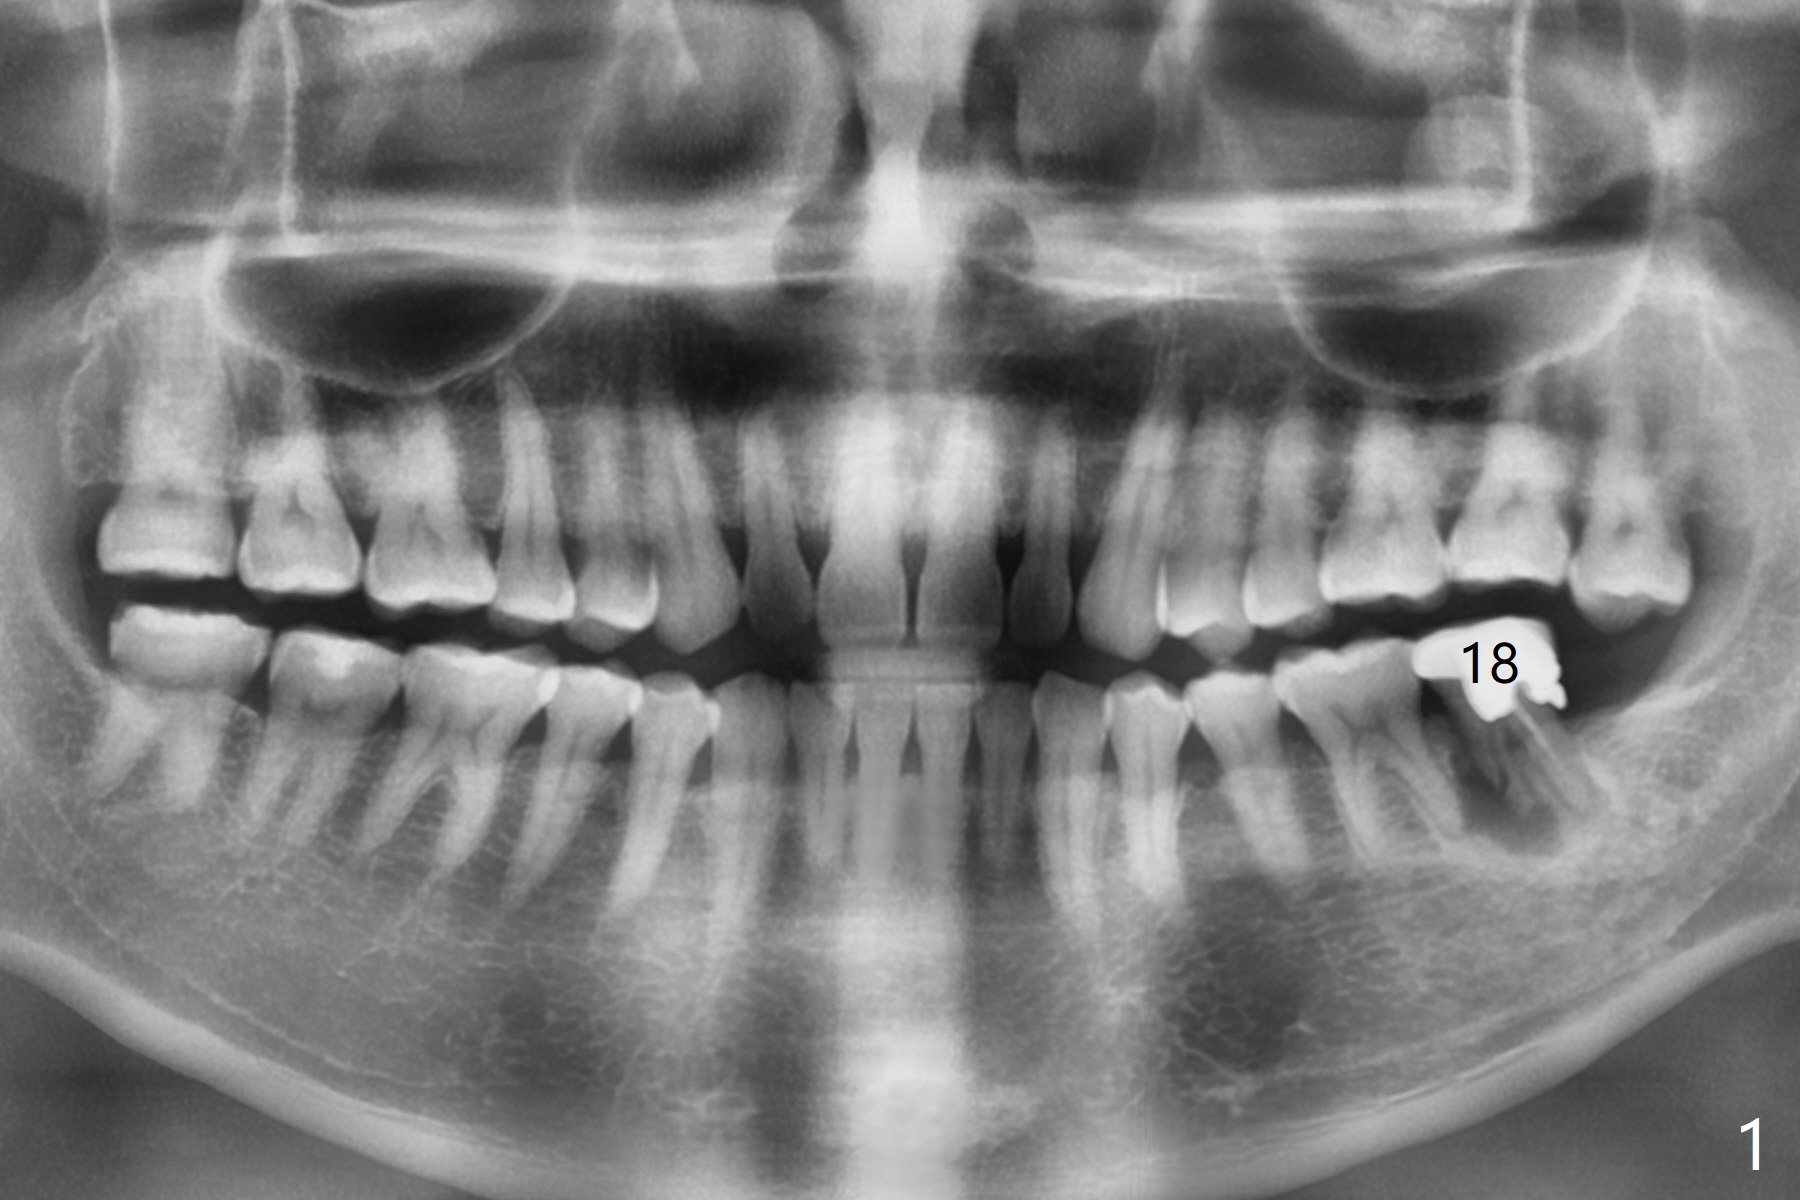

Mesial Root Fracture

A 35-year-old man has repeated pain at #18 (Fig.1). He is a bruxer with exostosis (Fig.2 *). It appears that the mesial root of the affected tooth has vertical fracture (Fig.1-4). A 5x11.5 or 13 mm implant is appropriate (11 or 13 mm FC, Fig.5). Draw blood for PRFx2/sticky bone.